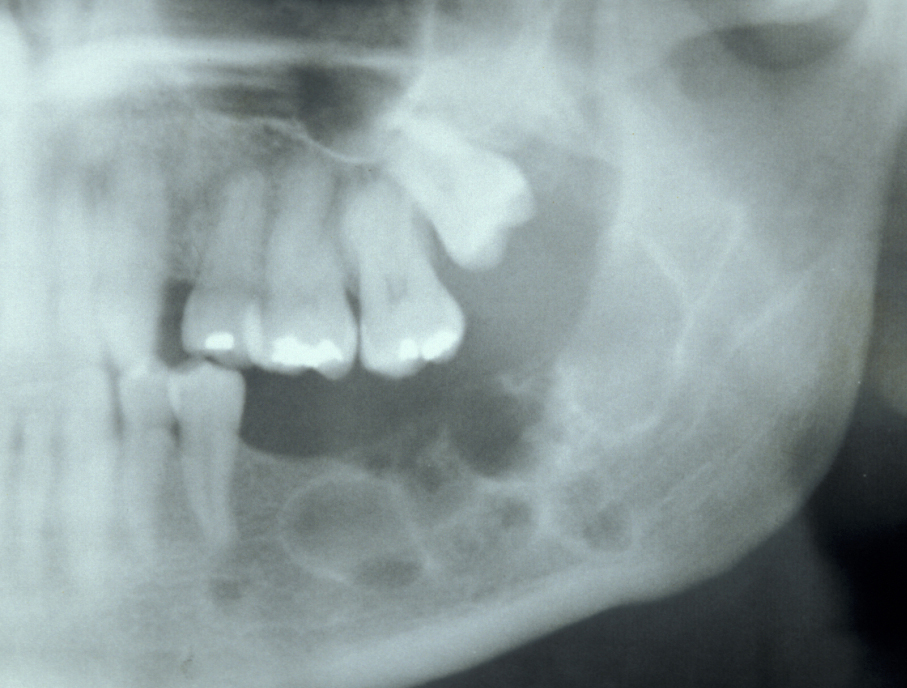

Unicystic ameloblastoma is a cystic swelling distinguished by resorbing adjacent tooth roots: histologically the lesion is an ameloblastoma but it has predominantly fluid contents. Figure 4 shows an example.

Figure 6: Unicystic amelobastoma resorbing tooth roots.

Follicular/plexiform ameloblastoma is a solid tumour, again found in the mandible. It is more aggressive in its clinical behaviour and resembles a solid tumour histologically (see Figure 5).

Figure 7: Sectional dental panoramic tomogram of the ‘soap bubble’ appearance of the solid variety of ameloblastoma.